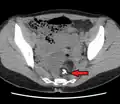

A complex cyst due to a dermoid as seen on ultrasound

A complex cyst due to a dermoid as seen on CT. Arrow points to bone or teeth.